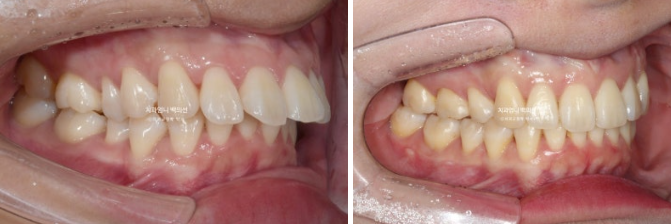

23.02-25.01

전 후 비교입니다.

총 치료기간은 1년 11개월이고 실제 장치를 낀 기간은 1년 9개월입니다.

윗니뻗침이 심하면 아랫입술이 윗니 뒤에 걸려 입을 다물었을 때 윗니 끝단이 살짝 보입니다.

입술이 편하게 안 다물리는 상태이고 이를 입술부전증 이라고 합니다.